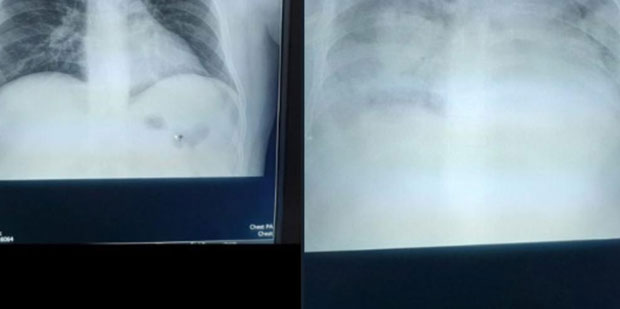

RUKOVODSTVO kragujevačkog Kliničkog centra podnelo je prijave protiv lekara hirurga iz ove zdravstvene ustanove V. Đ., koji se tereti da je podatke o preminulom pacijentu objavio na svom tviter-nalogu.

Kako nam je u sredu rečeno u Kliničkom centru, protiv njega je podneta krivična prijava zbog odavanja ličnih podataka pacijenta, jer je na društvenoj mreži objavio snimke njegovih pluća. Takođe, protiv njega su podnete još tri prijave nadležnim organima i službama, među njima i Lekarskoj komori.